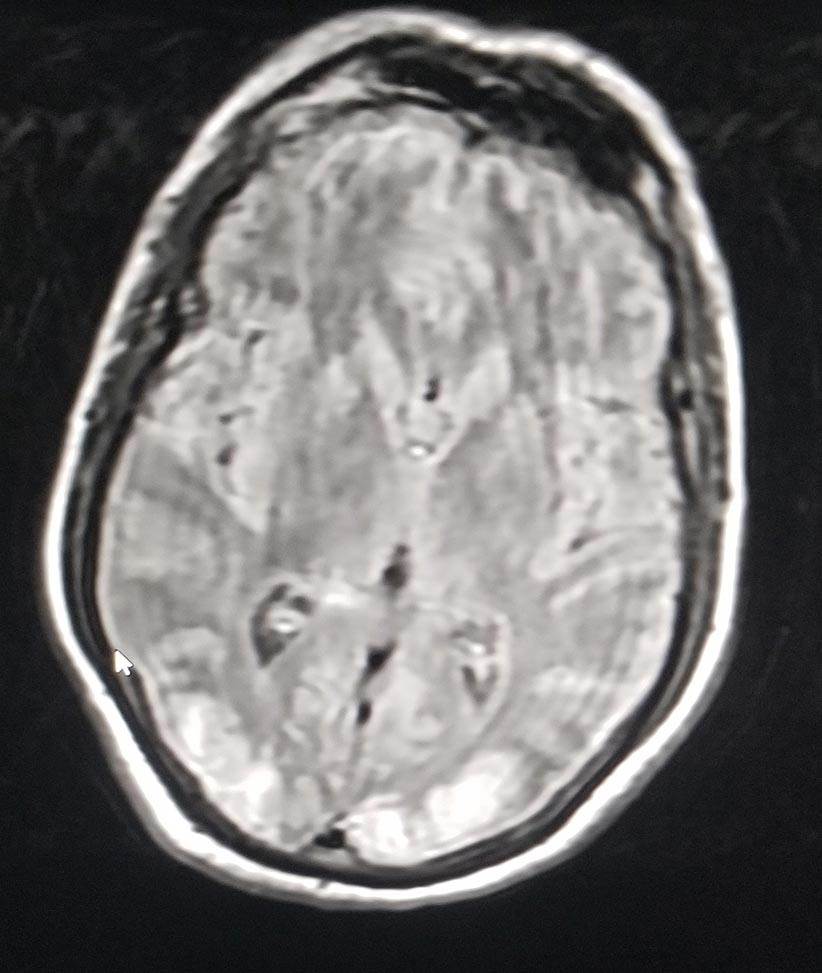

Según los doctores que atendieron el caso en el Hospital Auxilio Mutuo, al paciente se le realizaron varias tomografías computarizadas y resonancias magnéticas que mostraron insultos isquémicos multifocales en evolución en todo el territorio de perfusión de las arterias cerebrales posteriores con edema citotóxico que provocó borramiento de los surcos corticales y pliegue cerebeloso. Además, la prueba de hipercoagulación -para determinar si una persona tiene o ha formado un coágulo sanguíneo- fue positiva para PR-3 pero C-ANCA fue negativa.